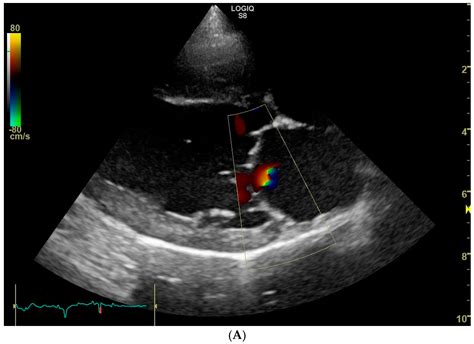

• Echocardiogram: This is the primary diagnostic tool for mitral regurgitation. It uses ultrasound waves to create images of the heart and assess the structure and function of the mitral valve.